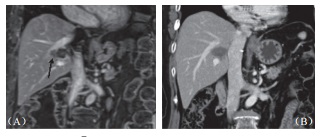

本研究中所治療之腫瘤均貼近血管,隨訪期間也未見血管狹窄或栓塞(圖3),影像上也未見受波及膽管進一步擴張或狹窄,只有一位在第9個月出現(xiàn)局部復發(fā)的病患,出現(xiàn)輕微膽管擴張,但無膽紅素上升之異常。在12個貼近膽囊及15個貼近腸胃壁的腫瘤消融之后,僅有一位(8.3%)在術后超聲中出現(xiàn)無癥狀的膽囊壁水腫,而在1個月后改善,無任何腸胃道受損或消化受影響的跡象。兩人術前曾放置膽管內(nèi)塑料質(zhì)支架,術后移除時經(jīng)檢視支架無損傷,移除后也不再黃疸。

圖3 55 歲男性肝癌病患在接受射頻消融后右肝靜脈及右側(cè)門脈旁復發(fā),(A)2cm×1.5cm 大小腫瘤(箭頭處)直接侵犯右肝靜脈;(B)消融后 6 個月血管內(nèi)及血管側(cè)腫瘤消失,僅余前度射頻消融遺跡,鄰近血管無損傷